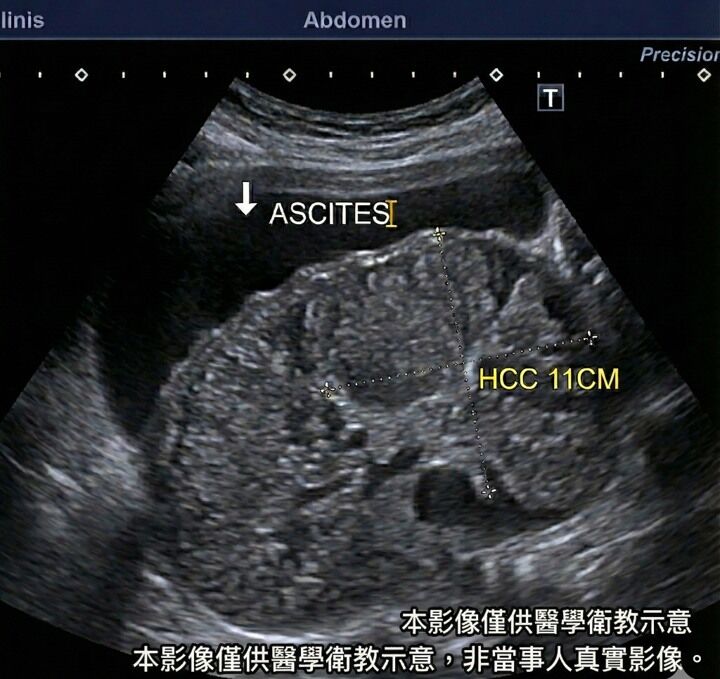

醫師緊急為患者進行超音波檢查,結果發現腹腔內充滿腹水,且肝臟已經嚴重硬化,更驚人的是還有一顆直徑達11公分的巨大肝腫瘤,確診為肝癌。卓韋儒表示,當患者平躺時敲擊腹部兩側會出現濁音,改變姿勢後聲音位置會跟著水流移動,這就是腹水的典型徵兆。

圖片來源:卓韋儒醫師臉書